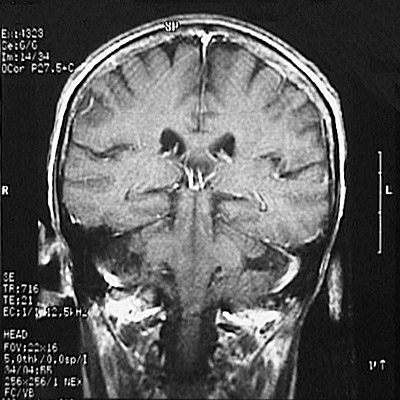

This is a normal coronal T1 weighted enhanced MRI scan demonstrating the parietal lobe and temporal lobe and cerebellar hemisphere and pons and middle cerebral peduncle and lateral ventricle and superior sagittal sinus and corpus callosum.